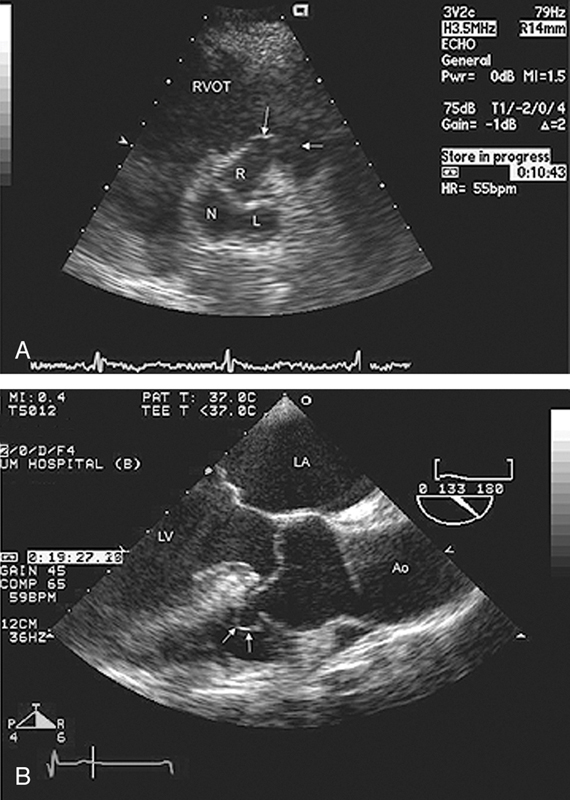

فحوصات تشخيصية لبعض امراض القلب والشرايين التاجية